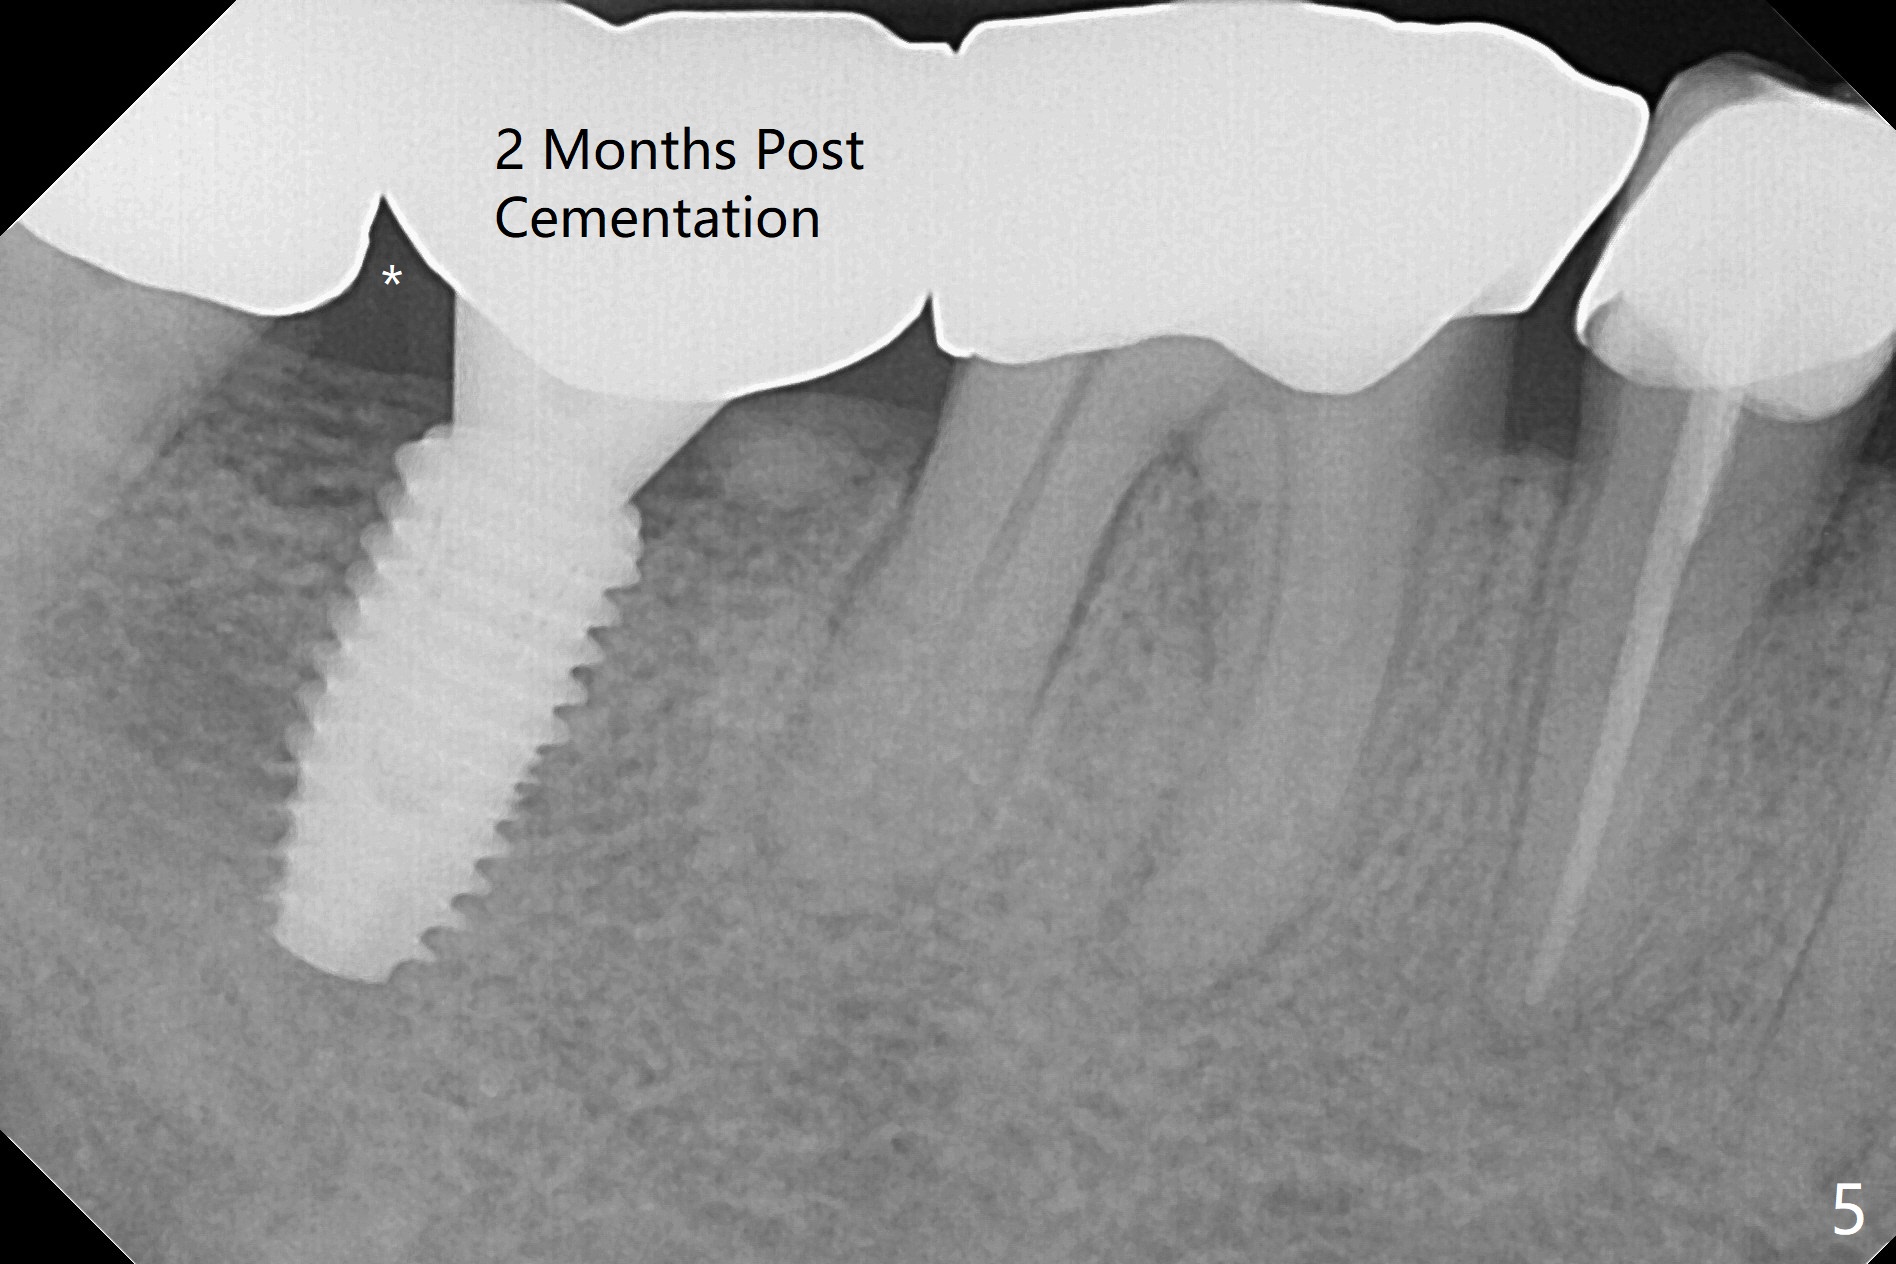

The edentulous ridge at #31 is anesthetized with one carpule of Lidocaine in an infiltration manner for guided surgery (Fig.1,2). In comparison, two or 3 carpules of Lidocaine are required for anesthesia for delayed implant placement without guide. It suggests that guided surgery is associated with less pain. Besides, the implant placed with guide has good trajectory and depth in a timely manner (Fig.3). Since the patient is a heavy bruxer with dislodgement of #30 provisional and #19 abutment screw loosening, a 5.7x4(3) mm cementation abutment is placed immediately so that a splinted provisional is fabricated for #30 and 31 for better retention. However, the gingiva around the implant at #31 is unhealthy 3 months postop (Fig.4). After impression, the provisional at #31 is sectioned without recementation for better oral hygiene. The distal gingival embrasure is large, associated with food impaction (Fig.5). Two years post cementation, the proximal contacts are trimmed (Fig.6 *) for pick up impression for crown repair. The implant and abutment contact is clearly shown with change in X-ray projection (Fig.7). When the new crown with flattened proximal contacts is being seated, it is tight mainly distal. After distal proximal contact adjustment, the crown is recemented without taking out crown/abutment for residual cement removal, because they may be unable to be completely seated because of the flattened larger proximal contacts (hand torque before impression).